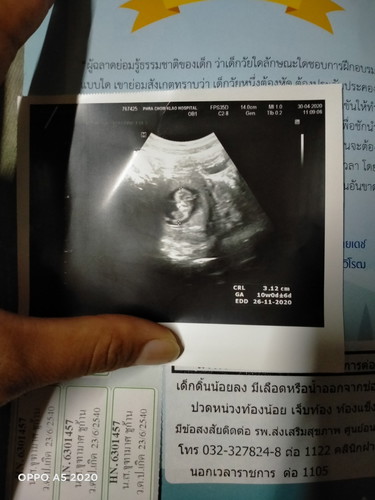

เราปวดท้องน้อยบ้อยมากวันนี้หมอซาวด์ดูหมอบอกว่ามดลูกน่าจะขยายตัว

เห็นตัวน้องแล้ววว.

แม่ท้อง